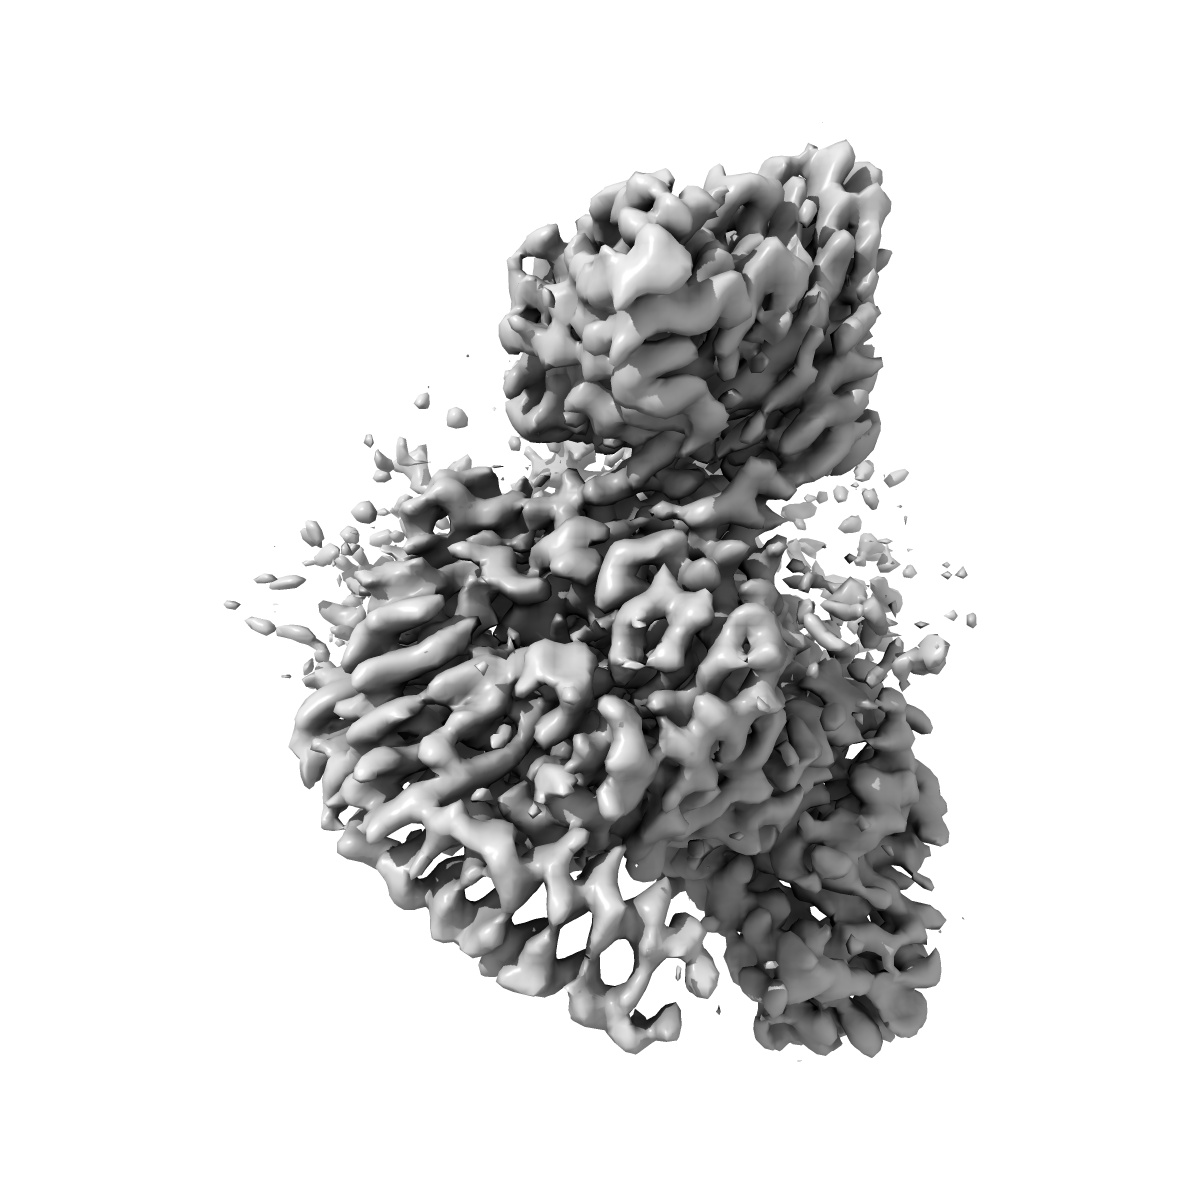

Cryo-EM Structure of the Prostaglandin E Receptor EP4 Coupled to G Protein

Single-particle3.5 Å

Sample: Cryo-EM Structure of Prostaglandin E Receptor EP4 Coupled to G Protein